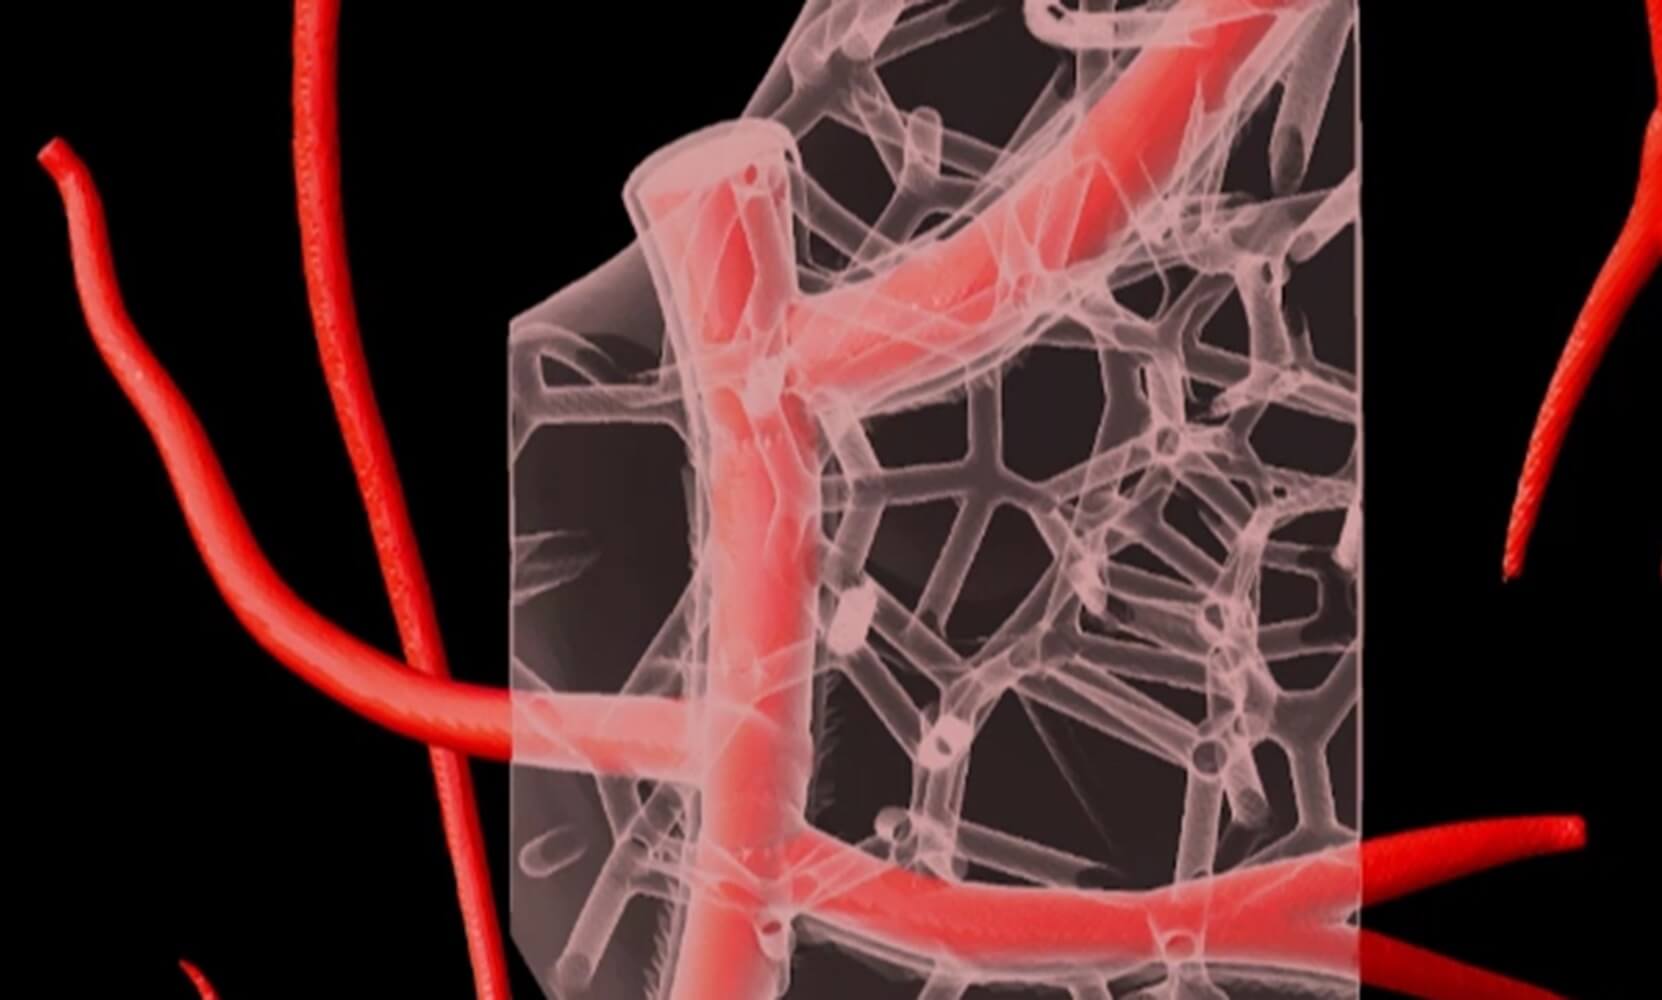

Die Mikrostrukturen menschlicher Gewebe und Organe lassen sich nicht so leicht nachbilden. Doch sie entscheidend, wenn es um die Funktion der Organe geht. Es ist schwierig, das zu Beginn der Prozedur noch flüssige Kollagen für das Grundgerüst in Form zu bringen. Die neue Methode von Andrew Hudson von der Carnegie Mellon University in Pittsburgh und seinem Team erlaubt feinste Mikrostrukturen aus Kollagen. So können die Forscher nun Organgerüste aus Kollagenfasern von nur 25 Mikrometern Dicke drucken. Zellbesetzte Organteile wurden mit der FRESH (Freeform Reversible Embedding of Suspended Hydrogels) getauften Methode angefertigt.

Das Bad in zähem Hydrogel beim 3D-Druck sorgt für winzige Kollagenstrukturen, die nicht aus der Form geraten und Hohlräume und Poren gedruckt werden können. Durch die Verkleinerung der Moleküle auf 25 Mikrometer nimmt die Auflösung der Teile zu. Ist der Druck fertig, härtet die Kollagenlösung aus. Das Organmodell wird erwärmt, wodurch das Hydrogel wegschmilzt. Die FRESH-Methode sorgt dafür, dass auch komplette Organteile, dessen Zellen, biologische Materialien und feinste Verästelungen von Gefäßen möglich sind.